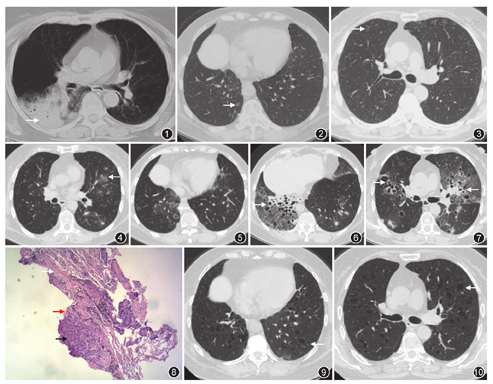

患者女,66岁,主因"间断咳嗽、咳痰9个月余"于2015年9月8日入院,患者9个月前因咳嗽,咳大量白色泡沫痰,无发热、呼吸困难,于外院行胸部CT(图1)示右肺下叶大片实变影、周边弥漫磨玻璃影,查血常规、血癌胚抗原正常,抗感染治疗9 d效果不佳,就诊于我院胸外科,考虑为肺癌,于2015年2月9日行右肺下叶切除及纵隔淋巴结清扫术,术后病理:中央型浸润性黏液腺癌,肿瘤大小约6 cm×6 cm×4.5 cm,支气管及血管断端干净,纵隔及肺门淋巴结未见转移,但肺泡腔内组织细胞聚集,术后分期为ⅡA(T2bN0M0)。患者仍有咳嗽咳痰,但较前好转。患者顾虑化疗相关不良反应,未同意行辅助化疗。4个月前患者胸外科门诊复诊,血癌胚抗原正常,胸部CT(图2,图3)示右肺多发囊性病灶,未予重视。2个月前复查胸部CT(图4,图5),患者肺内囊性病灶及实性结节病灶较前明显增多,肺功能:FEV1占预计值%为116.4%,FEV1/FVC为70.95%,TLC占预计值%为99.4%,DLCO占预计值%为72.8%,支气管镜检查镜下未见明显异常,左B3 BALF白细胞分类:巨噬细胞51%,中性粒细胞7%,淋巴细胞40%,嗜酸粒细胞2%,曲霉半乳甘露糖抗原检测0.168,涂片找抗酸杆菌阴性,细菌、真菌培养均阴性,巨细胞病毒DNA阴性,右B4支气管TBLB病理示肺泡间隔增宽,纤维组织增生,慢性炎症细胞浸润,部分肺泡腔扩张,其内可见较多组织细胞聚集。既往史:发现脂代谢紊乱5年,不吸烟,30年前因卵巢囊肿行子宫及双附件切除。

入院后9 d在CT引导下对左下叶后基底段囊性病变进行穿刺活检,病理示肺泡结构清晰间隔稍增宽,Ⅱ型肺泡上皮增生,肺泡腔内较多组织细胞聚集。后患者咳嗽、咳痰明显加重,咳大量白色泡沫痰,夜间不能平卧入睡,伴呼吸困难,无发热,抗感染治疗效果不佳。因患者诊断仍不明确,且入院34 d后再次复查胸部CT(图6,图7)示病变明显进展,于2015年10月12日第二次行支气管镜检查,内镜下未见明显异常,于左B6行TBLB,病理示肺黏液腺癌(图8)。

诊断明确后予培美曲塞及奈达铂化疗4周期,患者咳嗽、咳痰症状完全消失,胸部CT(图9,图10)示双肺磨玻璃及实性结节完全吸收,但仍残留双肺弥漫囊性病变。